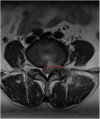

Methods: We included 285 patients with single-segment lumbar disc herniation treated using transforaminal endoscopy lumbar discectomy TELD from January 2017 to December 2019 at the First Affiliated Hospital of the University of South China. Patients were classified into early recurrence and non-early recurrence groups based on clinical symptoms and MRI reexamination. Imaging data (eg, disc height index (DHI), Pfirrman grades, base width, postoperative annulus-fibrosus tear size, cross-sectional area of the foramen (CSAF), etc.)were analyzed, and multivariate, binomial logistic regression was utilized to determine which factors were associated with early recurrence after TELD.

Results: A total of 285 patients completed surgery and clinical follow-up, during which 19 patients relapsed within 6 months postsurgery, for an early recurrence rate of 6.7%. There were statistically significant differences between DHI, Pfirrman grades, base width, postoperative annulus-fibrosus tear size, herniation sites, CSAF and Modic changes between the early recurrence and non-early recurrence groups (P < .05). On multivariate logistic regression,the degree of disc degeneration (OR = .747, P = .037), CSAF (OR = 5.255, P = .006), degree of Modic change (OR = 1.831, P = .018) and base width of the herniation (OR = 4.942, P = .003) were significantly correlated with early recurrence after TELD.

Conclusions: Postoperative annulus-fibrosus tear size, DHI, and location of the disc herniation were associated with early recurrence after TELD. Increased base width of the herniation, severe disc degeneration, decreased CSAF and Modic change were risk factors for early recurrence after TELD.